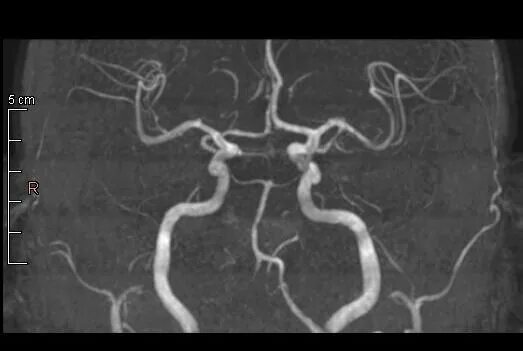

Гипоплазия интракраниального сегмента